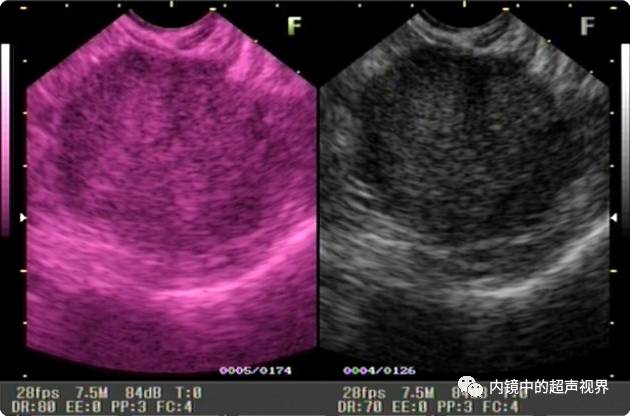

再说伪彩,它把黑白图像处理成黑橙、黑绿、黑蓝、黑粉等图像,一定程度上改变了图像的视感,类似于FICE、iSCAN等后处理光学染色功能,萝卜白菜各有所爱,喜欢哪个直接拿走。

胰头占位